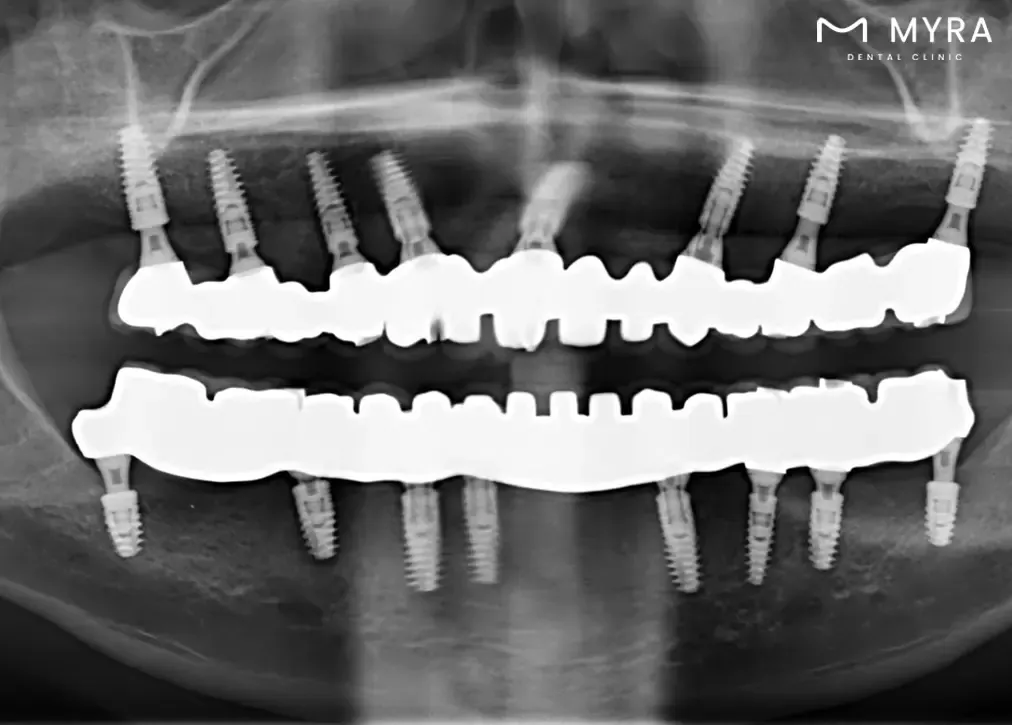

A 3D tomography X-ray shows a comprehensive view of the entire mouth, offering detailed insights into dental and jaw structures. The imaging method helps doctors better understand dental or jaw problems and come up with effective treatments by showing internal structures, bone density, soft tissues, and nerve distances. It makes it easier to diagnose dental problems such as cavities, buried teeth, fractures, bone defects, and other issues. It serves as a valuable tool in treatment planning, especially for dental implant placement, orthodontic procedures , and various oral health assessments , ultimately enhancing the success of treatments.

The Sirona 3D Dental Tomography is very useful because it combines different tomography layers into a single image that ensures all parts are visible, from the tooth's crown to the area between the teeth. The technology goes beyond traditional 2D X-rays, allowing for the viewing of hidden details that are crucial for diagnosis, treatment planning, and follow-up stages of oral and dental health.

The Sirona 3D Dental Tomography is frequently used for various purposes, including determining bruises, planning and following up on implant surgeries, detecting bone damage in advanced gingival diseases , and assessing joint disorders. The device is instrumental in cases involving cysts and tumours related to teeth and bones, determining the position of buried teeth before surgical procedures, and monitoring children's dental development and growth.

The Sirona 3D Dental Tomography's capacity to generate precise 3D images that aid in the diagnosis of conditions such as buried teeth, abnormal canal numbers, fractures, and cyst spread further emphasises its role. Its benefits extend to providing better image quality and higher accuracy, offering clear views of bone and soft tissues with a low radiation dose, and ensuring a quick and painless solution for patients.

Better Diagnosis and Treatment Planning: Sirona 3D Dental Tomography provides high-quality, three-dimensional images of the entire mouth, offering a comprehensive view that aids in the accurate diagnosis of dental and jaw problems. Its enhanced visualisation contributes to more effective treatment planning.

Comprehensive Examination of Oral Health: Sirona 3D Dental Tomography covers the entire mouth in a single image, offering a holistic view of oral health. Its comprehensive examination helps in identifying a range of issues, from bruising and root canal problems to joint disorders and salivary gland diseases.

Sirona 3D Dental Tomography allows dentists to gain a more in-depth understanding of dental and jaw-related issues. The three-dimensional images enable precise and accurate diagnoses of conditions such as tooth decay, buried or impacted teeth, fractures resulting from trauma, bone defects, and the periodic assessment of implants.

The procedure aids in treatment planning by offering a higher level of detail and accuracy. Dentists configure root canals, measure root canal dimensions, and conduct detailed assessments of bone density, sinuses, and joints. The technology helps in the planning of dental implant procedures, offering a three-dimensional evaluation of the jawbone structure.